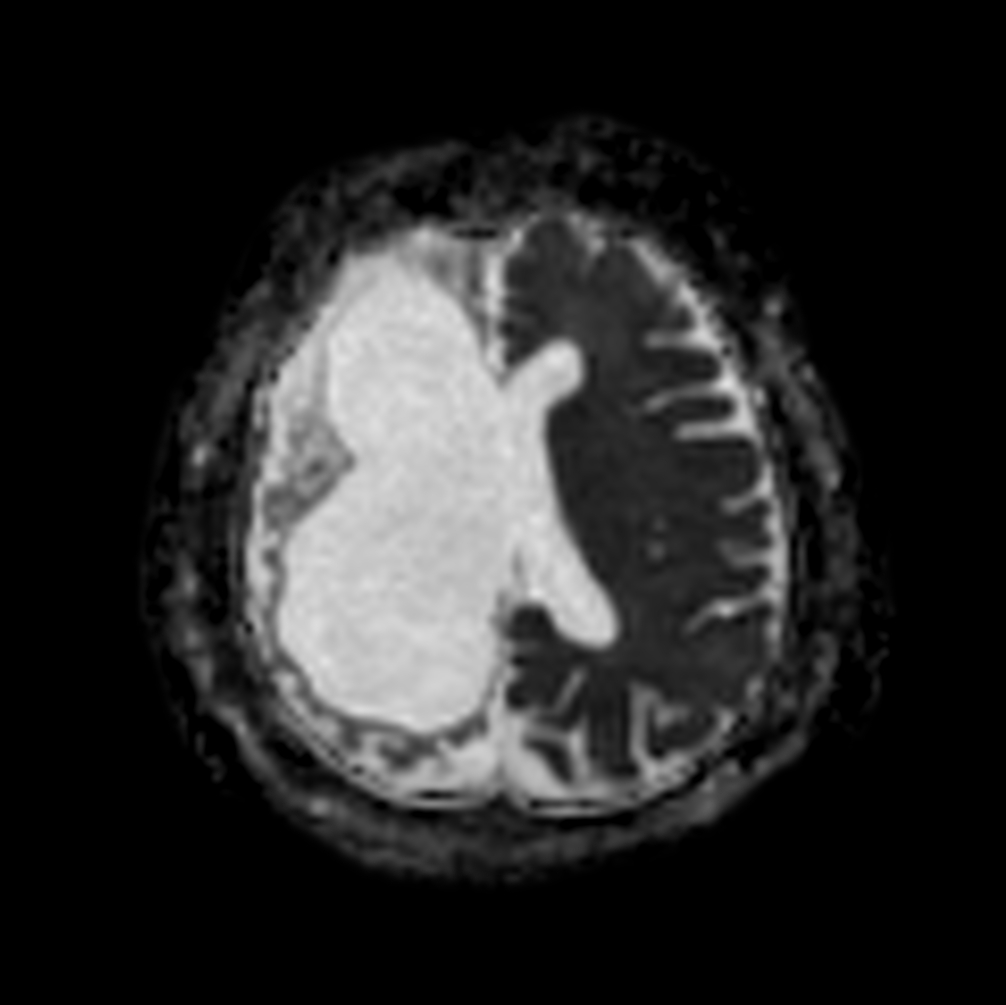

Axial 3D BrainVIEW FLAIR (without Compressed SENSE)

Axial 3D BrainVIEW FLAIR (Compressed SENSE)